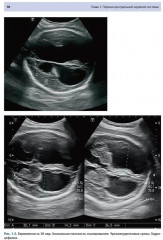

💳 Оплатить за товар можно при получении 🇰🇿 Есть бесплатная доставка по Казахстану от 1 дня 🎁 Копите бонусы с каждой покупки Одной из актуальных проблем современного акушерства является выявление пороков развития плода. Несмотря на активное развитие современных методов медицинской визуализации, каждый третий случай перинатальной смертности имеет различные варианты структурной или хромосомной патологии плода. Во многом это обусловлено субъективной интерпретацией получаемых ультразвуковых срезов, отсутствием единой методологии акушерского исследования. Данное учебное пособие посвящено вопросам стандартизации акушерского исследования в различные сроки гестации, представлены варианты нормы и патологии различных систем плода, предложена современная классификация пороков развития плода, алгоритм дифференциальной диагностики. Учебное пособие предназначено для практикующих специалистов ультразвуковой диагностики в области акушерства, пренатальной диагностики и акушеров-гинекологов. |